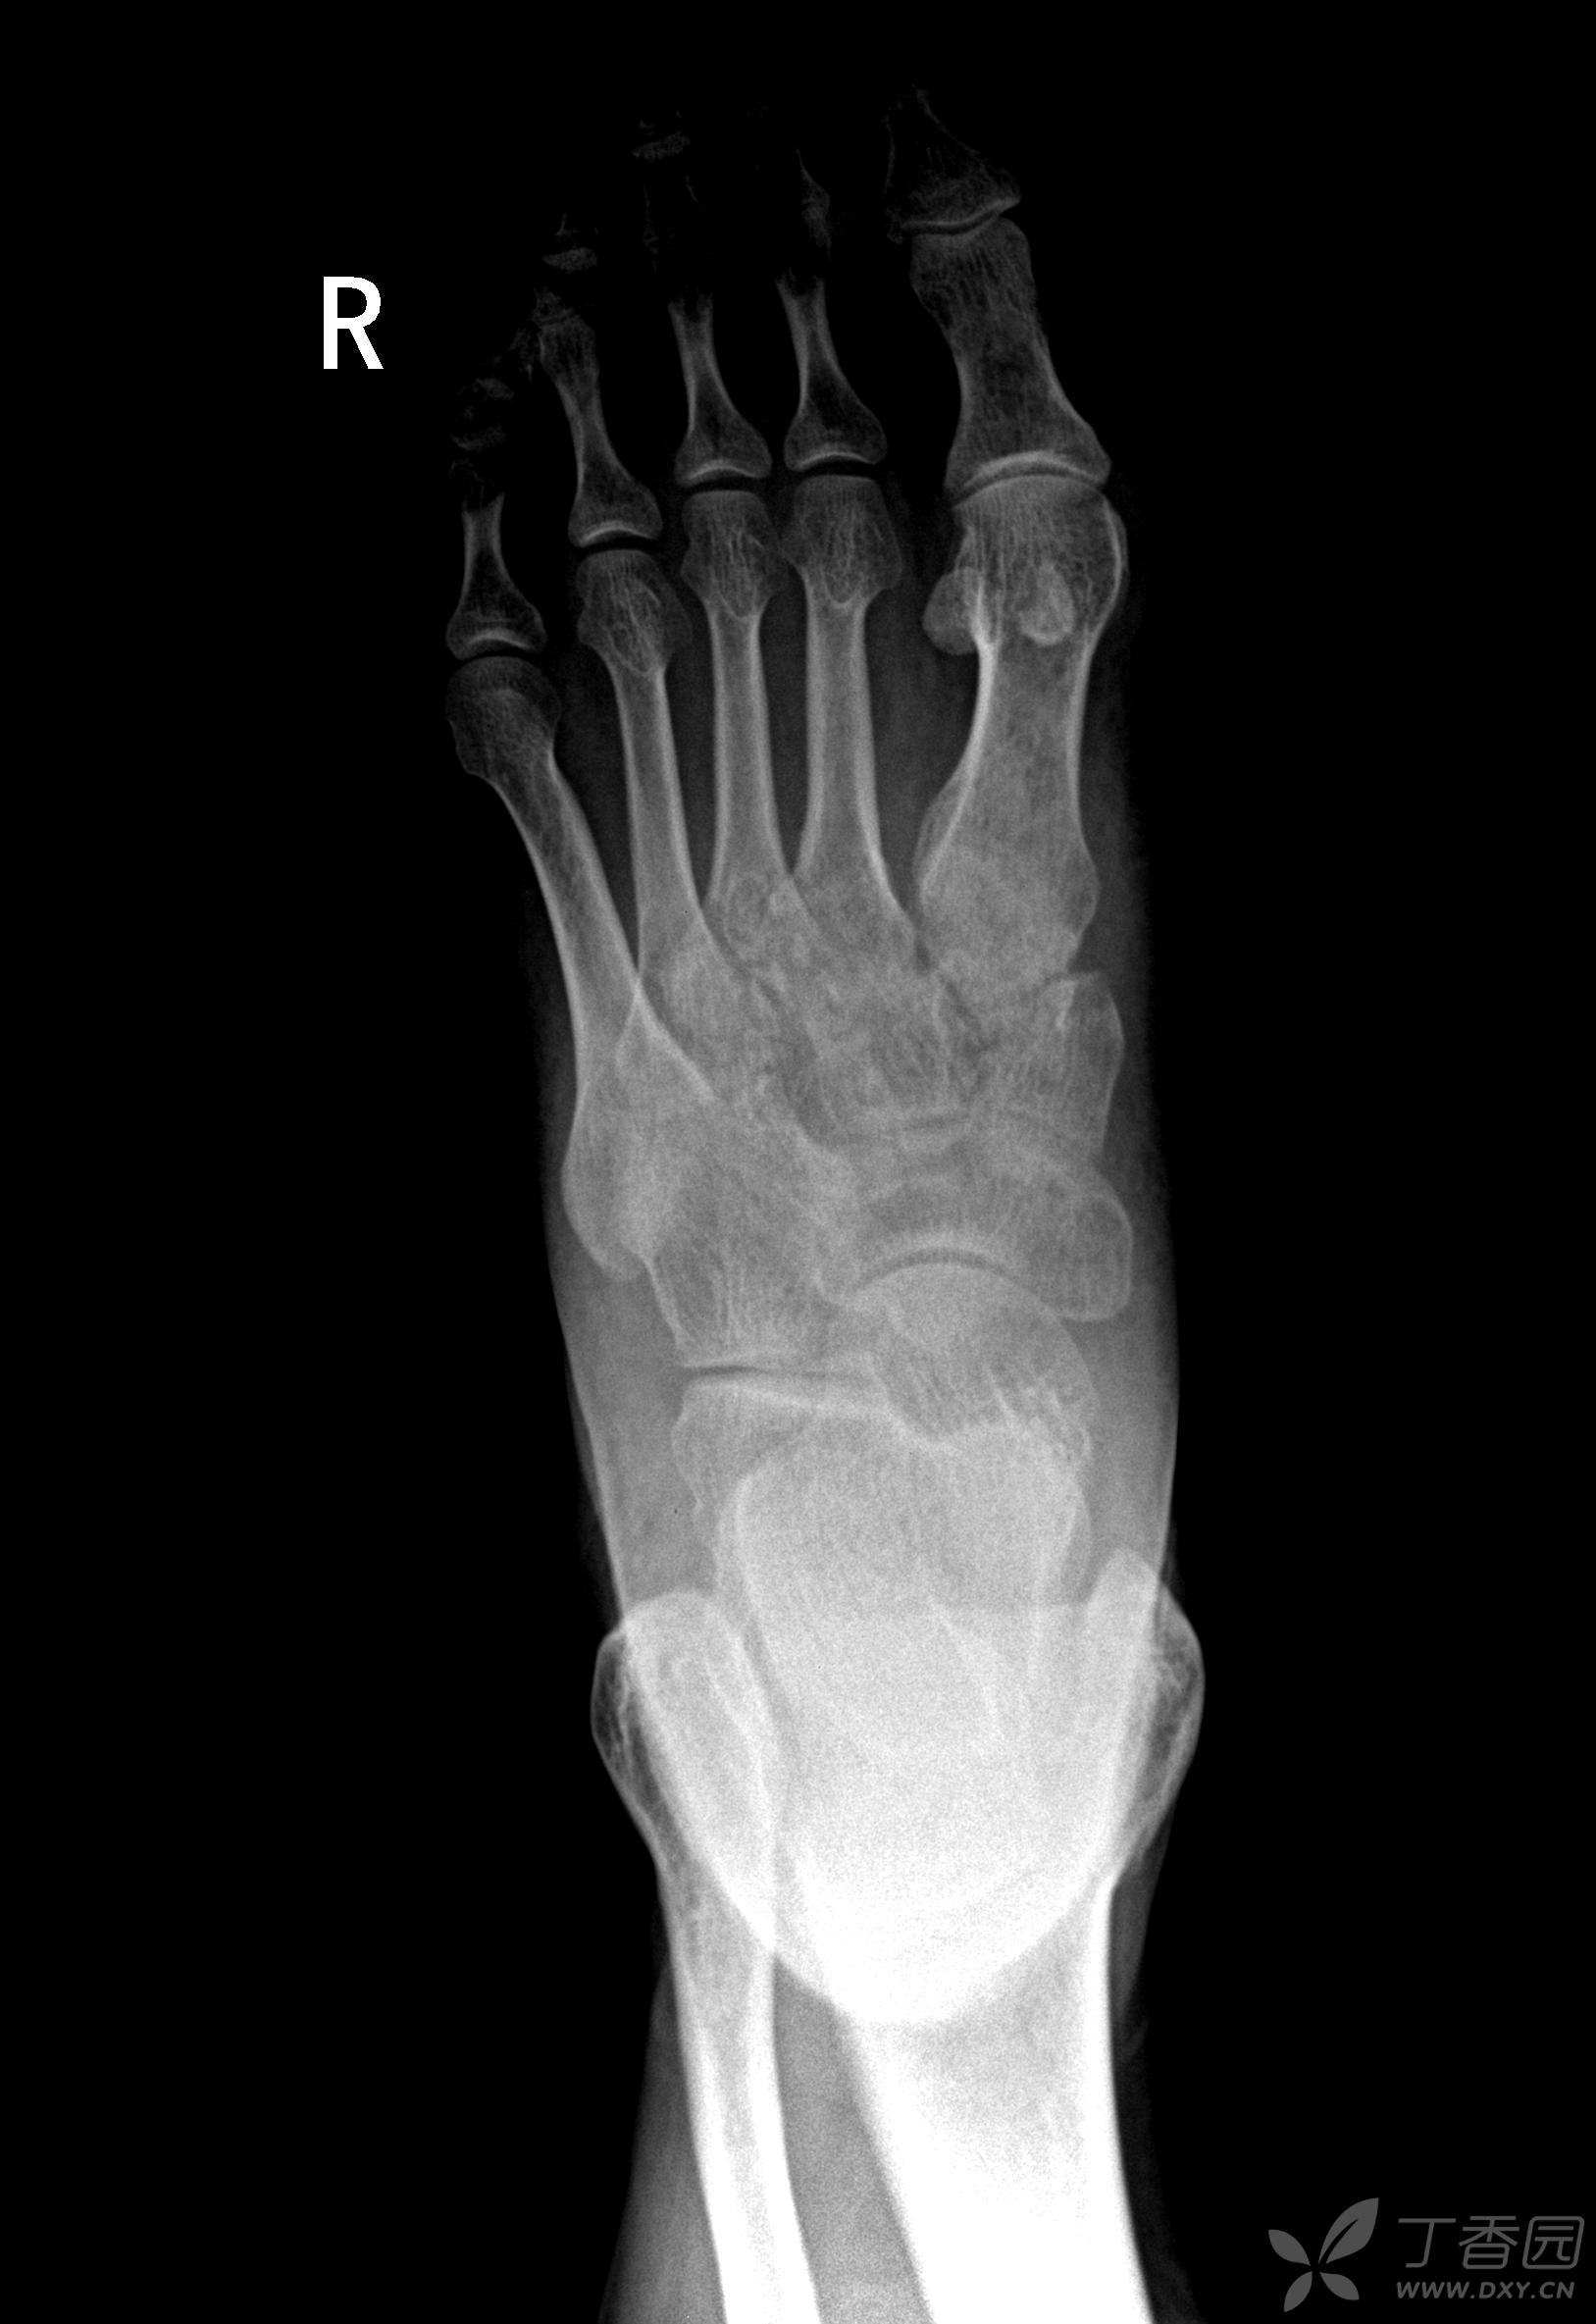

请教各位10765右足正斜位片